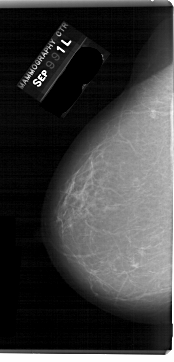

A_1138_1.LEFT_MLO

DATE_OF_STUDY 9 9 1991

PATIENT_AGE 54

DENSITY 2

LEFT_MLO LINES 6871 PIXELS_PER_LINE 3781 BITS_PER_PIXEL 12 RESOLUTION 43.5 NON_OVERLAY

FILE: A_1138_1.RIGHT_MLO.OVERLAY

TOTAL_ABNORMALITIES 1

ABNORMALITY 1

LESION_TYPE MASS SHAPE IRREGULAR MARGINS MICROLOBULATED

ASSESSMENT 4

SUBTLETY 2

PATHOLOGY MALIGNANT